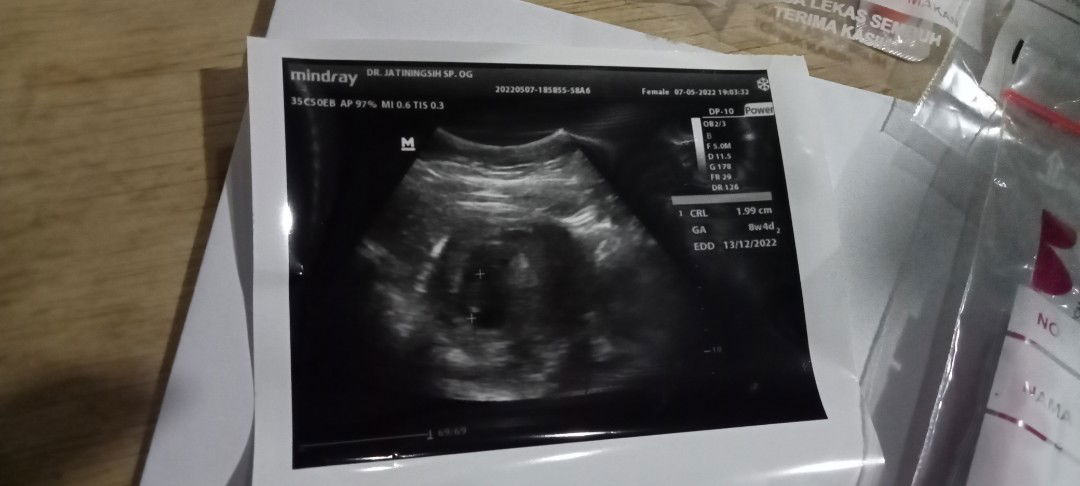

kalau saya masih tm 1 tau positif tespek tgl 3 lgsung usg di dr pertama katanya sdh 6 minggu hanya kantong uk 0.41, kata dr 1 balik lg untuk cek tgl 17, pas tgl 17 rupanya dr 1 sedang cuti, saya cari alternatif lain yg kata orang dr senior dr 2, di dr 2 saya sdh positif tp 5mgg5hari dg ukuran masih kantong sebesar 1.71 cm. skrg saya lg galau dan penasaran janin saya sdg terbentuk blm🥺